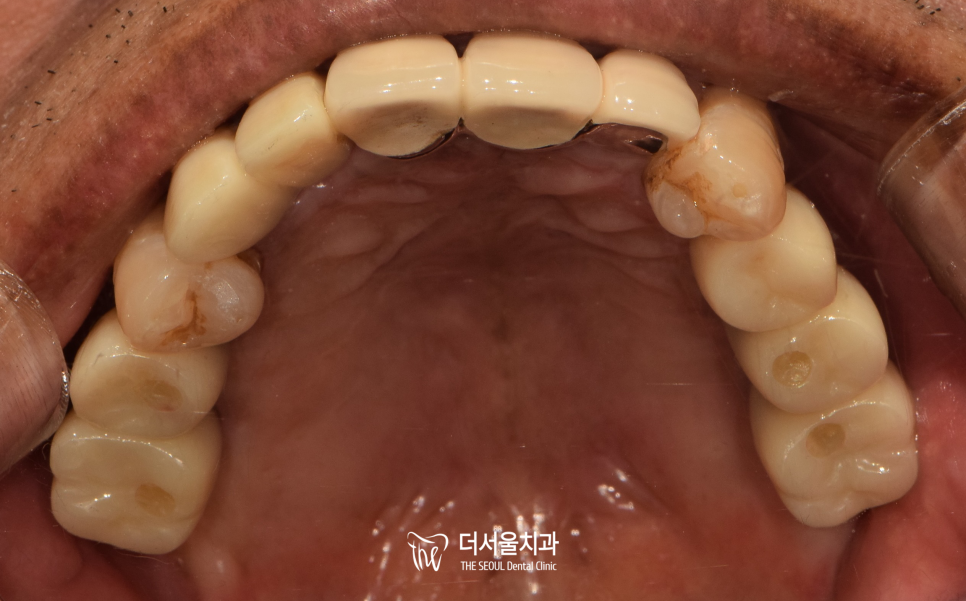

일정 기간을 거쳐

픽스처가 단단하게 유착된 결과를 확인한 후

정교하게 제작된 보철을 올려드리며

치료가 마무리되었습니다.